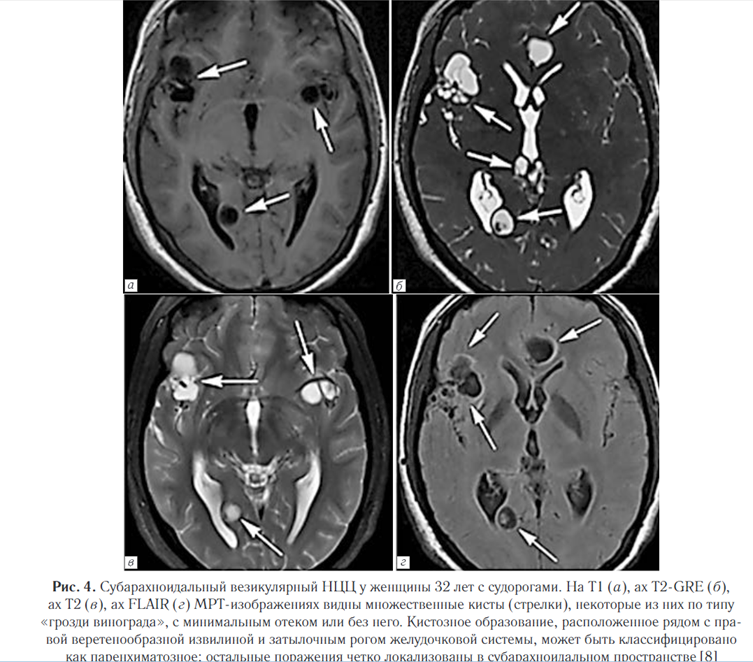

Субарахноидально-цистернальный НЦЦ поражает субарахноидальные пространства и прилегающие мозговые оболочки, которые представляют собой наиболее распространенную локализацию паразитов (рис. 4).

Проявляется в виде объемных поражений, которые могут стать причиной гидроцефалии (состояние может быть вторичным по отношению к базилярному арахноидиту).

Кисты также могут вызывать отек прилегающего вещества мозга с глиозом и васкулитом [8]. Внутрижелудочковый нейроцистицеркоз. Составляет от 0,7% до 33% всех случаев НЦЦ, часто сочетается с субарахноидальным.